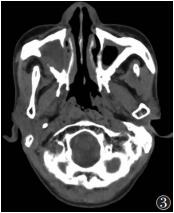

骨质增生14例,其中内侧壁受累4例,外侧壁10例,表现为窦壁较均匀增厚,窦腔轻度缩小。骨质破坏7例(图 2,3),其中内侧壁受累5例,外侧壁受累2例,表现为骨质吸收、缺损,周围有软组织肿块。

| 图 3 男,68岁,真菌性上颌窦炎。右侧上颌窦内软组织影充填,左侧上颌窦黏膜环形增厚,双侧上颌窦壁明显增厚,右外侧壁破坏,周围有软组织肿块 |

2.2.4 病变周围情况单侧病变同时累及同侧筛窦10例,累及同侧鼻腔7例(图 2)。双侧病变均同时累及鼻腔,其中双侧9例,单侧2例;同时累及双侧筛窦6例,单侧筛窦3例。窦腔骨壁增厚25例,骨质破坏7例,其中累及内侧壁5例,外侧壁2例。筛窦骨质破坏2例。上颌窦窦口扩大9例。累及筛窦者为筛窦气房密度增高,窦腔闭塞,其内见斑片状高密度影。累及鼻腔者鼻腔内软组织影充填,密度不均,其内见多发斑片状、结节状及团块状略高密度影,鼻道闭塞。累及鼻后孔4例。